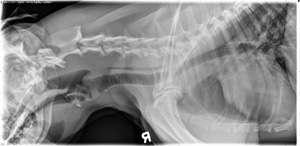

12 year old Golden Retriever

Today's case is a 12-year-old male neutered Golden Retriever. Owner noticed left thoracic wall mass. Post your comments! … [Read more...]